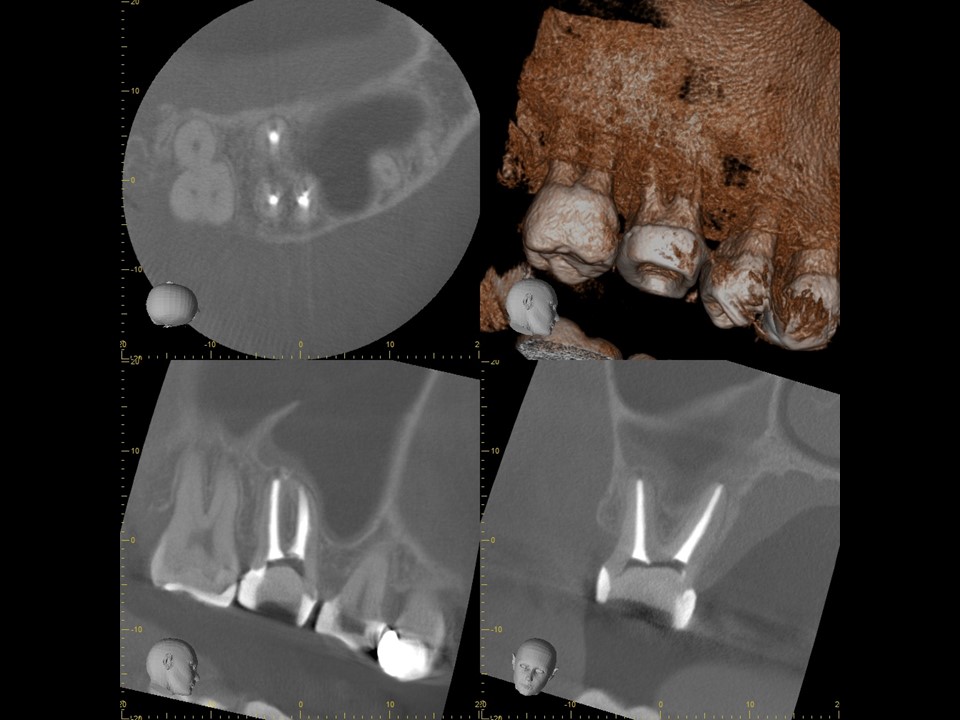

初診時CT画像。上顎洞に当該歯の部位に一致するX線不透過性の亢進を認める。繰り返し根管治療を行ったためか、根尖部は破壊されて太く開いている。また、湾曲した根管を何度も治療を行ったため、根尖部のパーフォレーションを認めた。